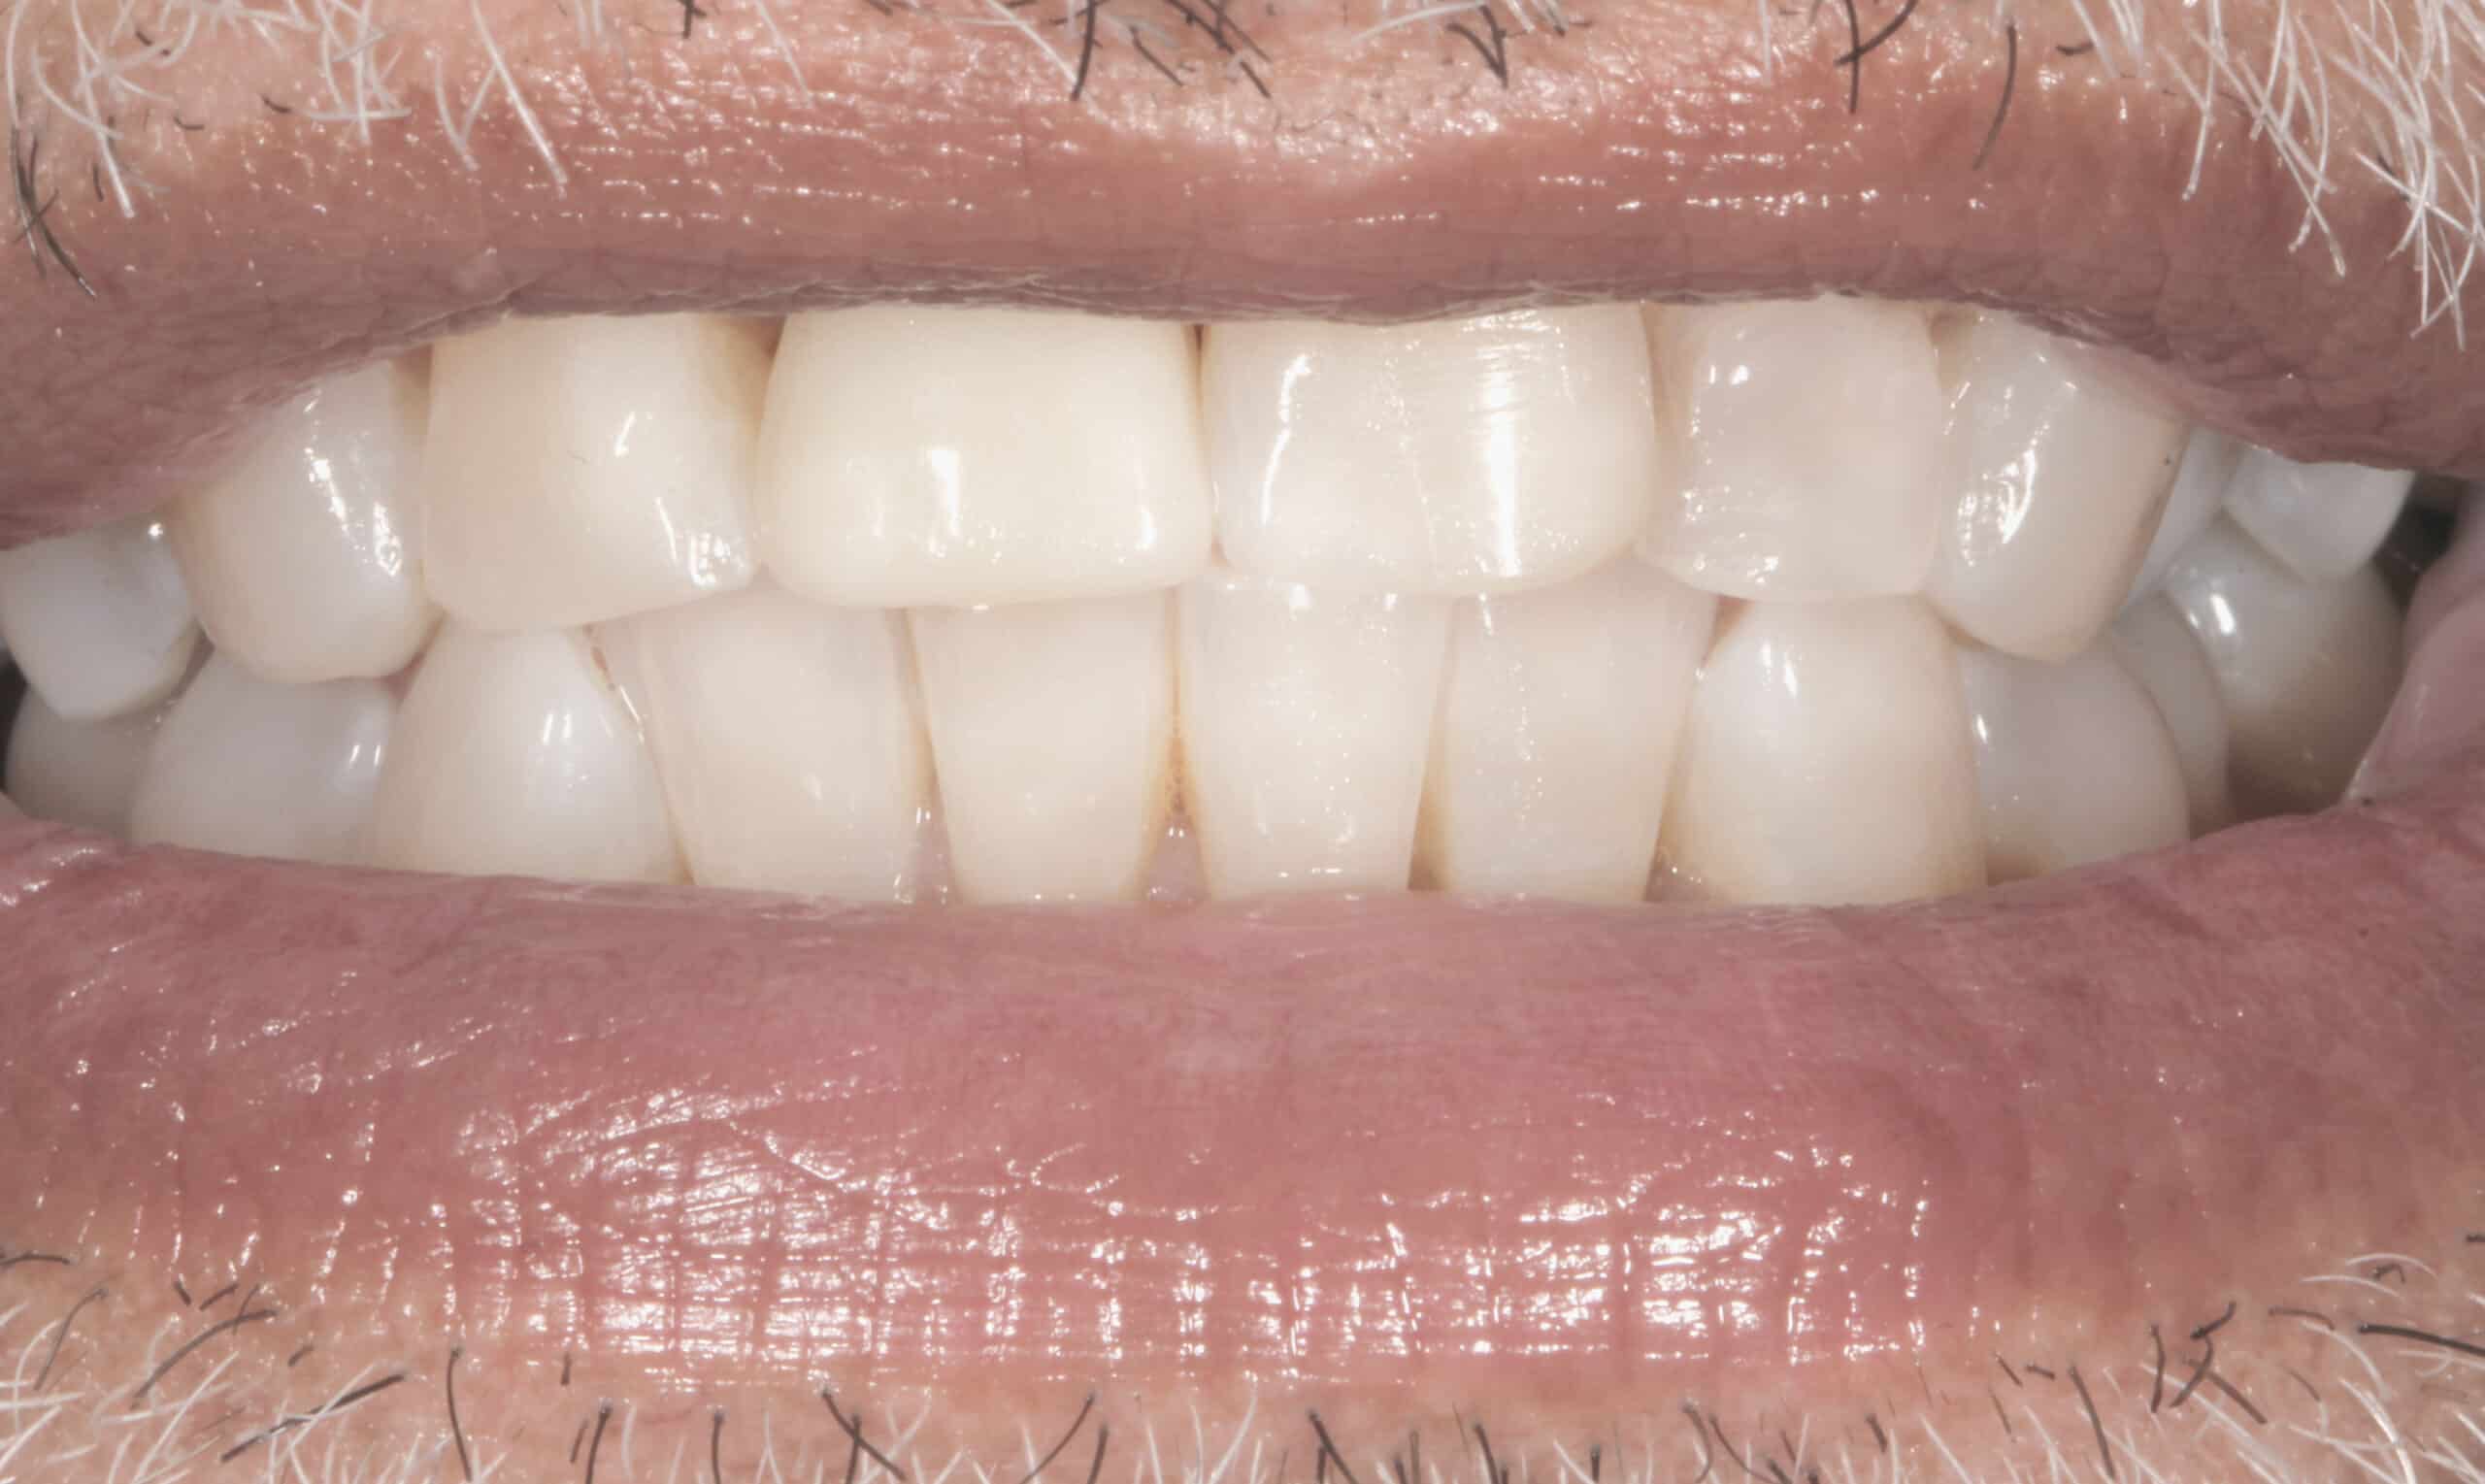

Our master lab technician crafted a beautiful porcelain crown to cement on top of the patient’s root canal and rescue post. Once the crown was cemented it blended in with his natural teeth beautifully.